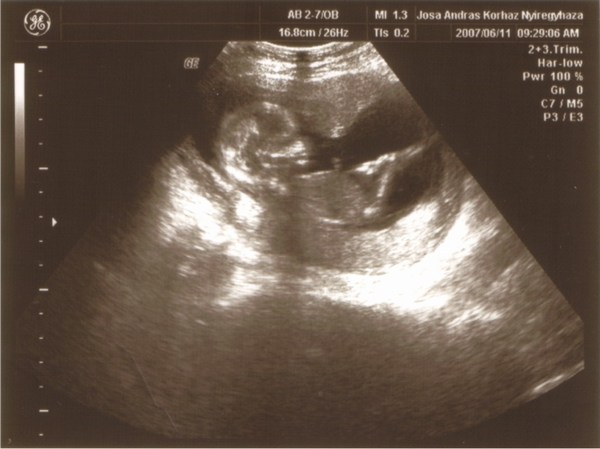

Végre fel tudom tenni a képét a kis Tündékénknek!:)Ímeeeee: Kép KisNyuszi:)

Nagyon szépen látszik a kis pocakja...fejecskéje....lábacskái...stb.

Tegnap mi is voltunk uh.-on....és most apuci is bejöhetett nagyon élvezte ez volt az első hogy láthatta a kis csemeténket mocorogni a képernyőn:)